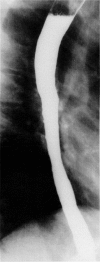

Diffuse intramural pseudodiverticulosis of the esophagus is a rare cause of dysphagia. A 19-year-old patient with a long history of recurrent episodes of food impaction was diagnosed with diffuse intramural pseudodiverticulosis. The clue to diagnosis is a critical and thorough review of the barium swallow. Treatment is aimed toward dilatation of strictures and treatment of inflammation.